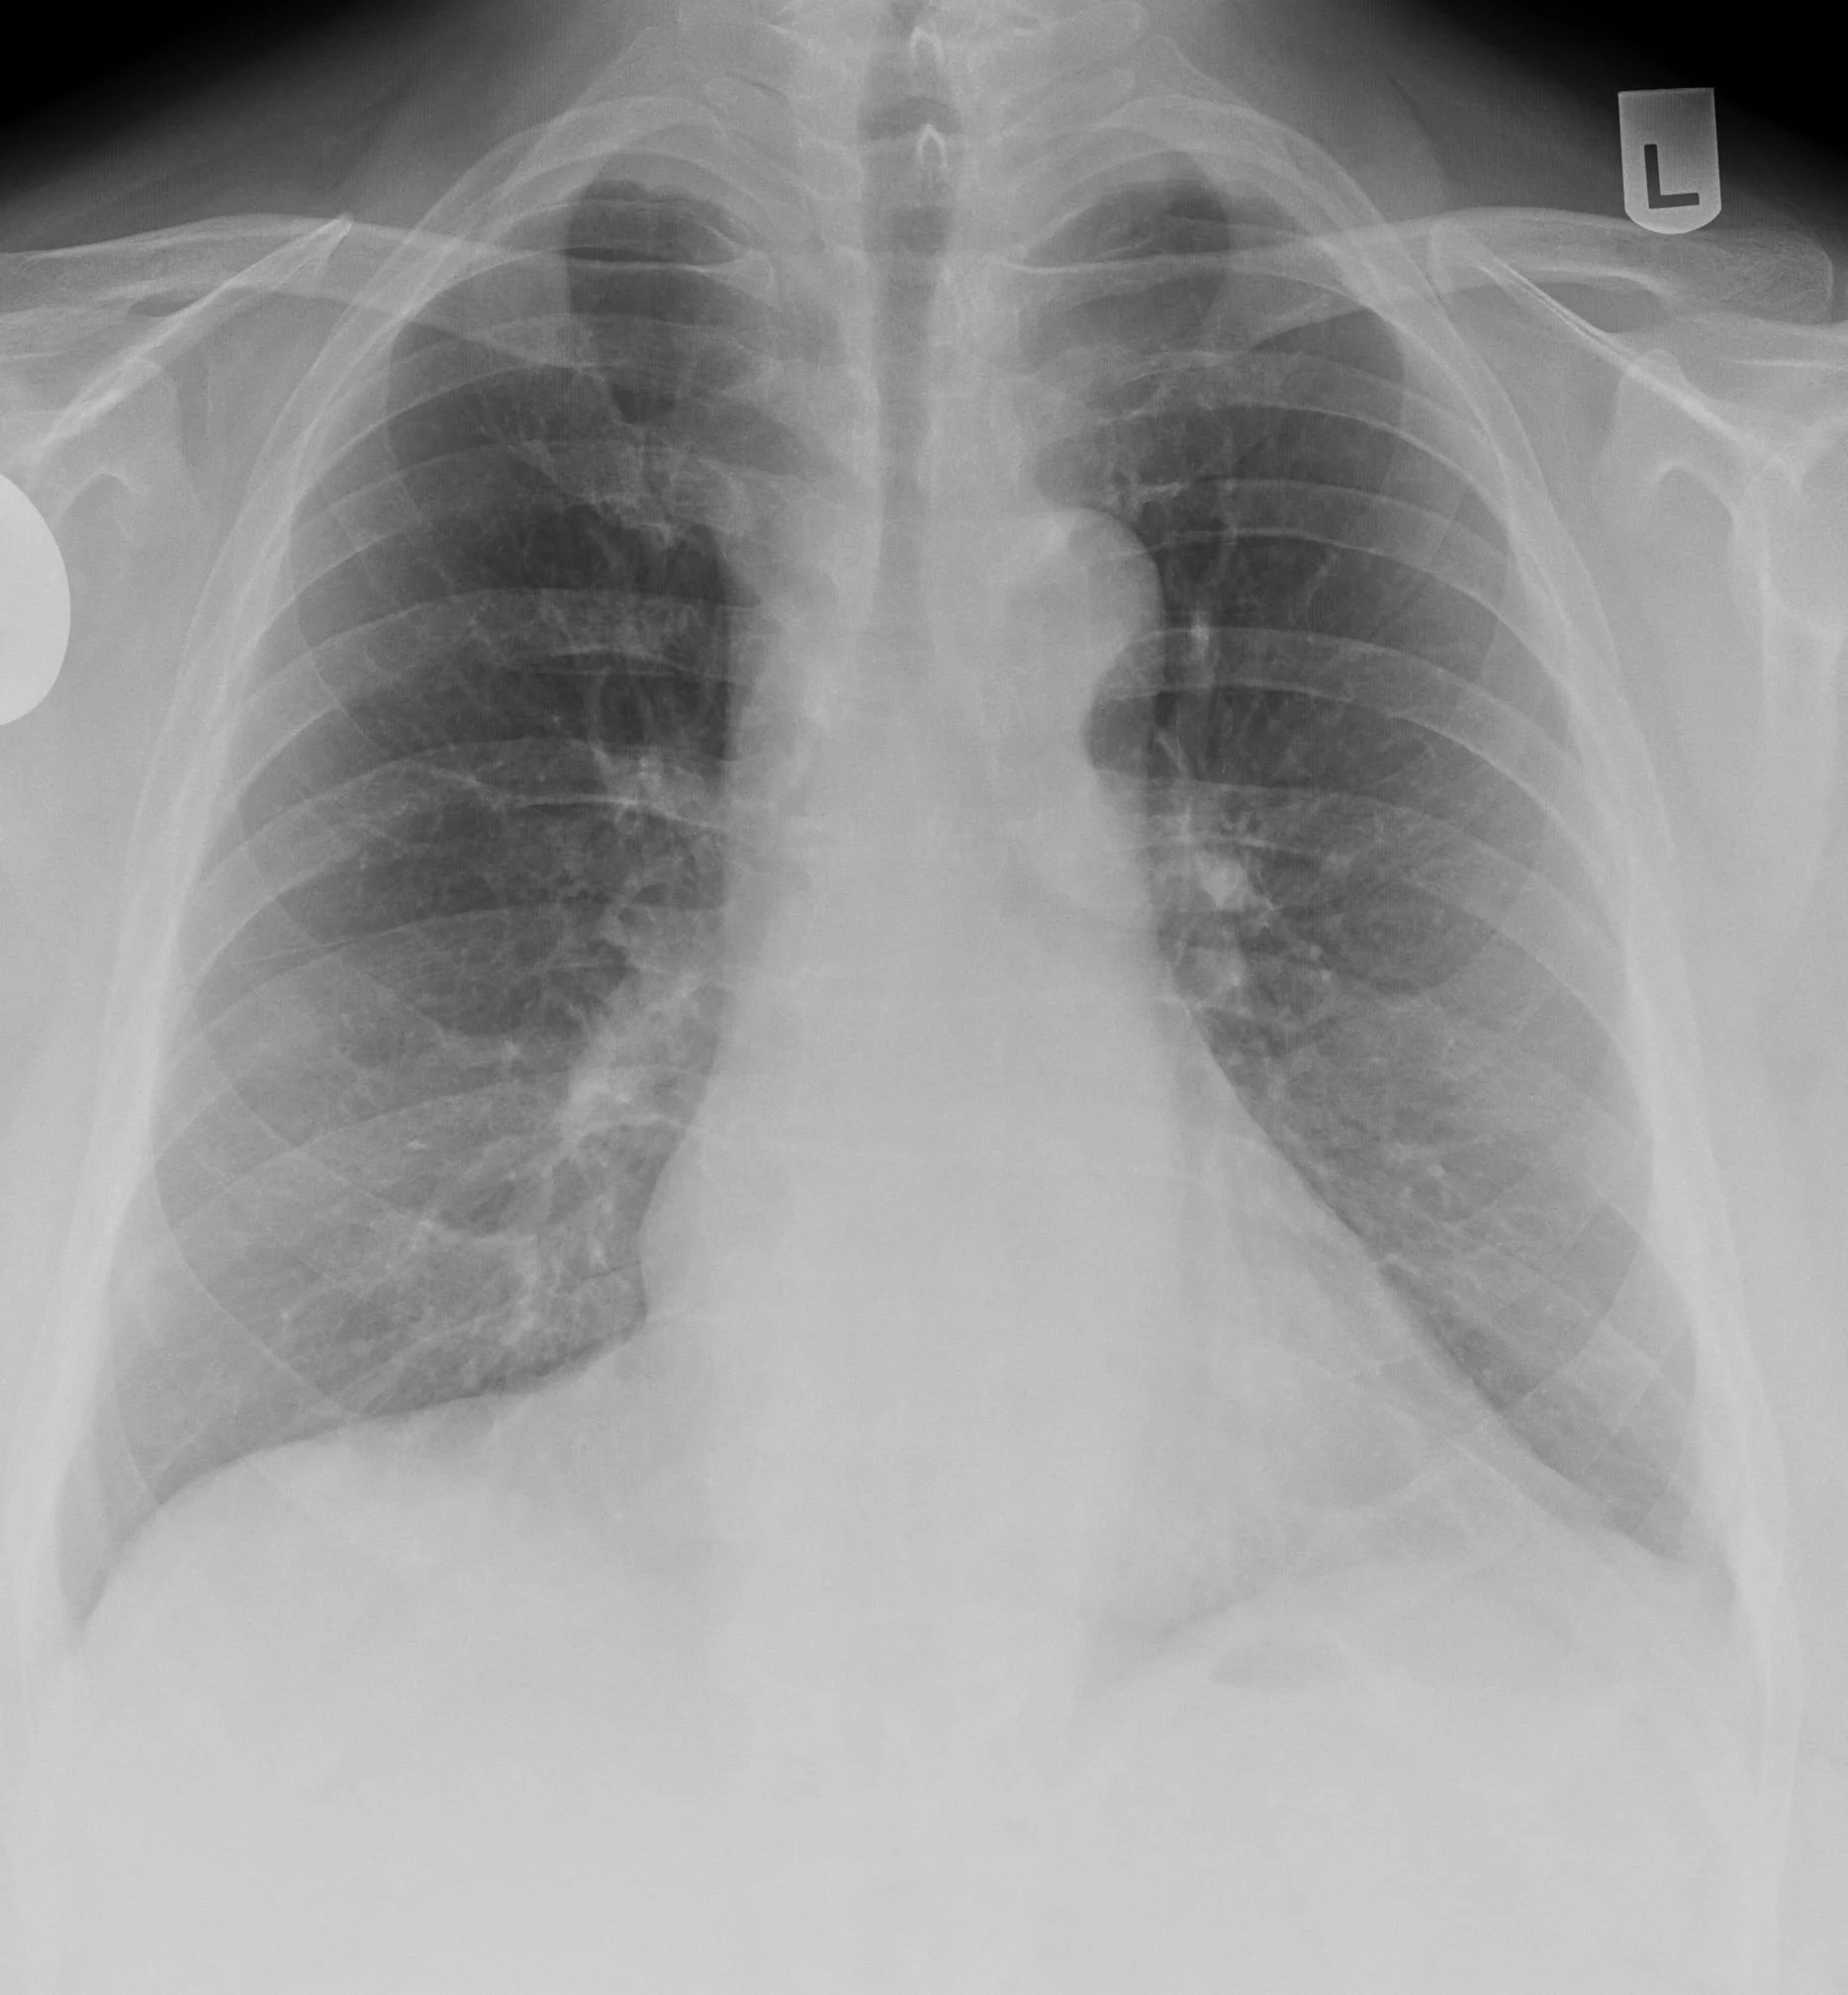

Snoopy Sign

• Seen in pericardial agenesis

• Will see

• Elongated and protruding left heart border

• Subtle lucency between the pulmonary artery and aorta (because no longer have pericardium which extends superiorly to bridge the two so you are basically seeing the borders of the vessels clearly

• Lucency between left heart border and diaphragm